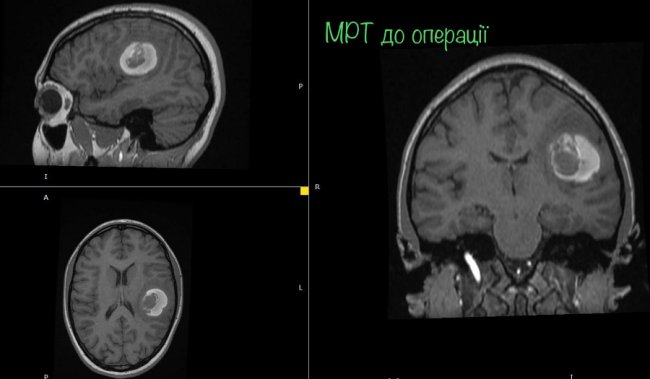

На МРТ виявили пухлину головного мозку з крововиливом в лівій домінуючій (важливішій) півкулі, в якій, власне, окрім центрів, які рухають кінцівками однієї половини тіла, розташований дуже важливий центр мови.